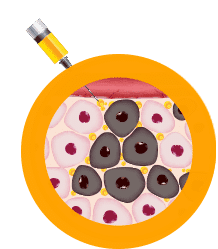

Step 1

Cancer is identified in the body.

Step 2

DNA-based interleukin-12 (IL-12), a naturally occurring protein, is injected directly into the tumor.